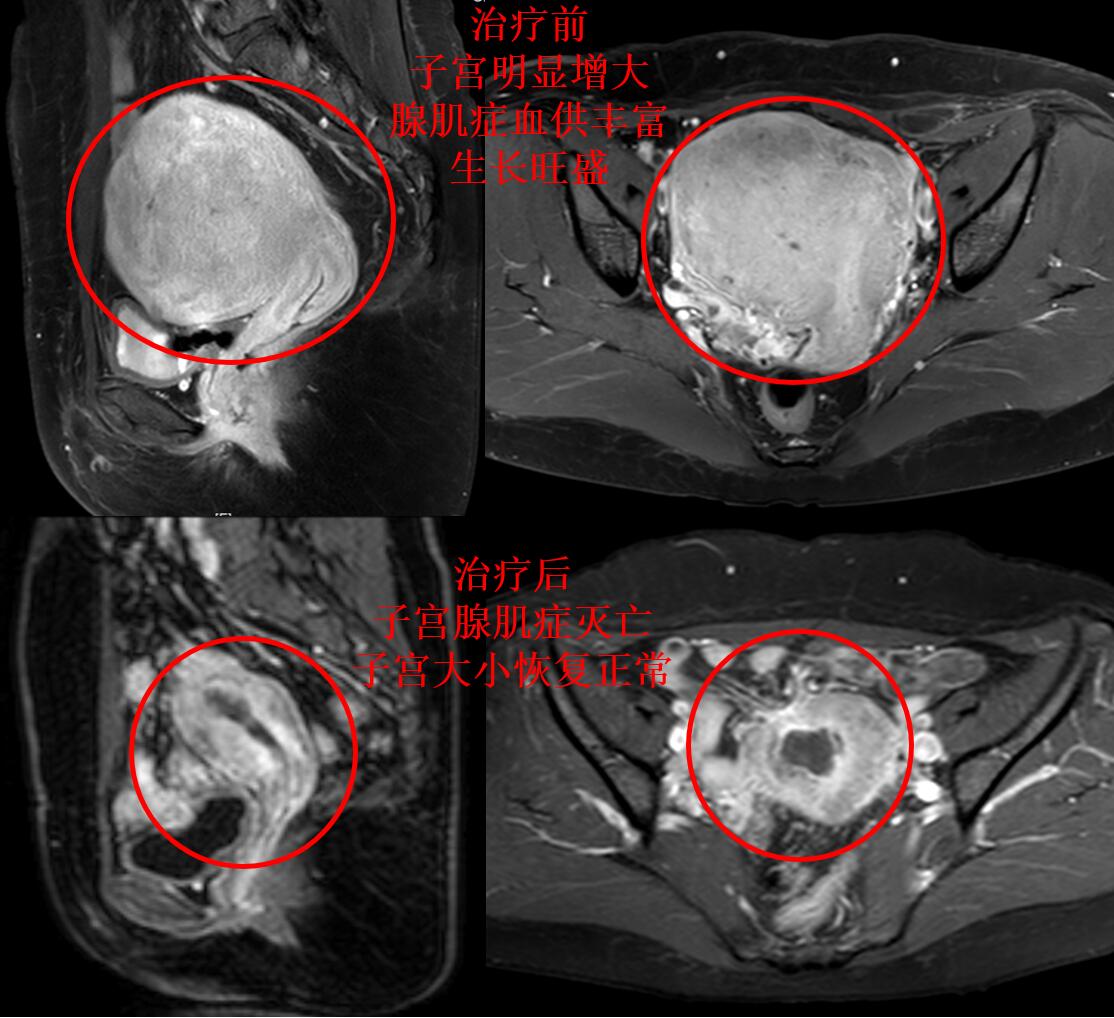

我们医院的蓝护士,8年前逐渐出现痛经,痛经在可以忍受的范围,不用服用止痛药,定期复查超声显示子宫逐渐增大。二胎后痛经逐渐加重,服用孕激素治疗,疼痛部分缓解,但月经老是拖尾,身体也逐渐发胖。近1年痛经再次加重,月经量增多而且经期延长十几天,月经还没干净几天,下一周期月经又来了,体重也严重超标。蓝护士就诊后考虑选择我院介入科的介入微创治疗,门诊磁共振检查显示:子宫明显增大(13.1*11.2*9.7cm3),腺肌症弥漫整个子宫,腺肌症病灶血供丰富。

介入微创栓塞治疗后第2天,蓝护士即可下床步行活动。治疗后2个多月蓝护士来例假,无痛经,月经量明显减少,6天干净。3个月后复查磁共振显示:子宫腺肌症灭亡,子宫缩小(如下图)。